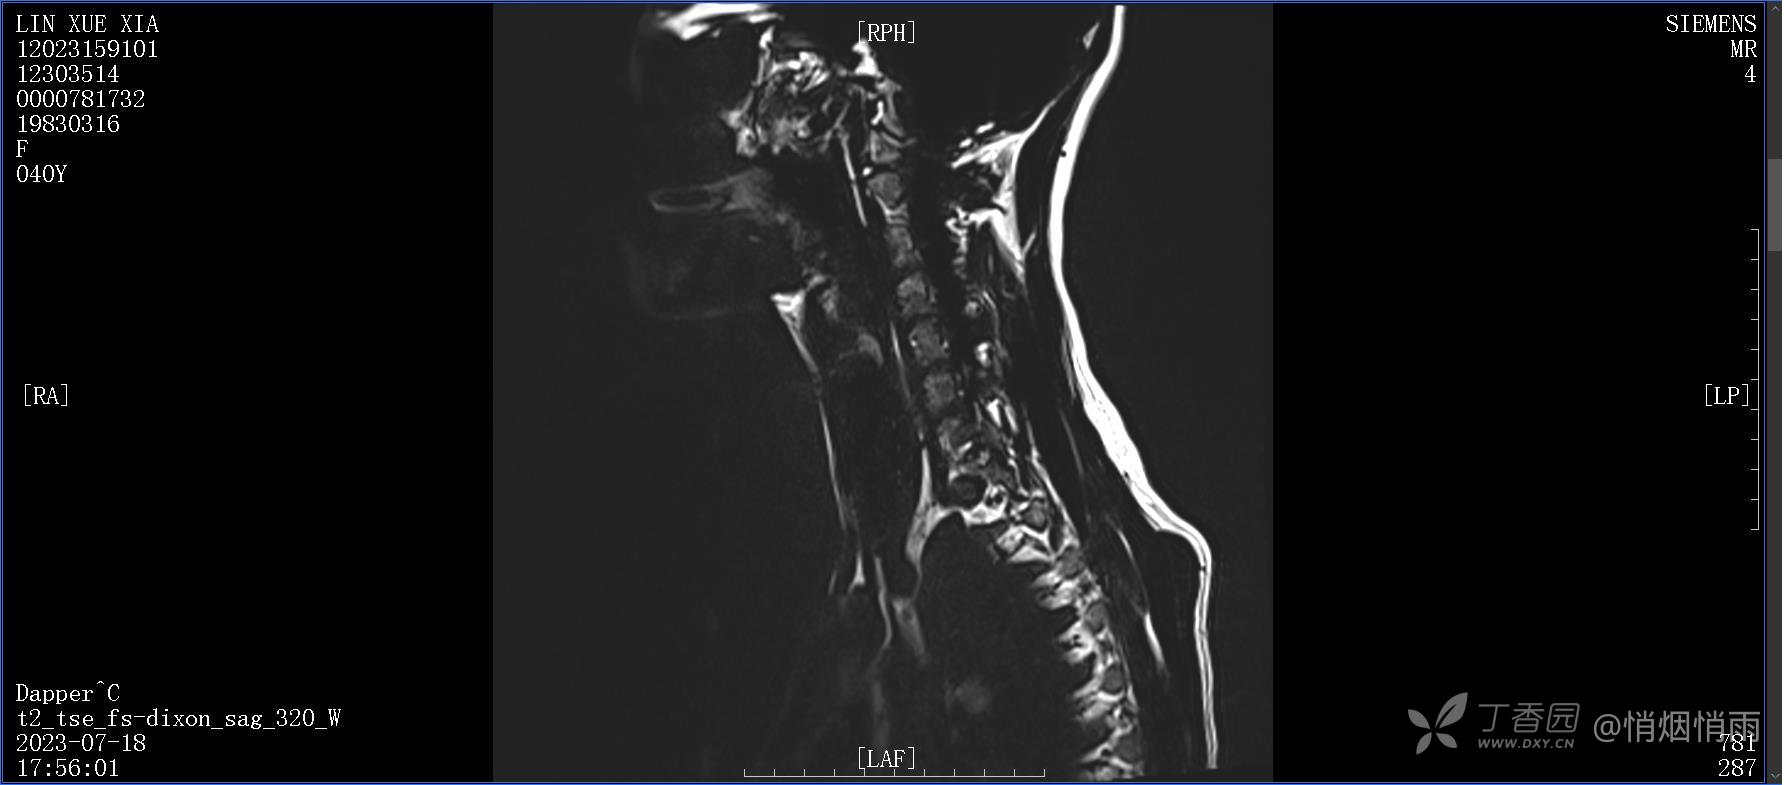

NeurothinkerZ 推荐患者女性,40岁,因右肩背部疼痛班活动受限4日余入院(2023-07-17)。

病史:入院前4天无明显诱因突然感右肩背疼痛伴随活动受限,自行口服依托考昔、艾瑞昔布等药物治疗,院外应用肩关节局部手法按摩等,均无明显改善。外院门诊诊为颈椎病。自诉既往多次“胸椎小关节紊乱”于当地诊所行手法按摩,治疗后好转,否认慢性疾病病史、外伤史、手术史,诉青霉素过敏,无其他药物食物过敏史,否认吸烟史、饮酒史,月经正常,经量正常。

目前的诊断,暂时依据辅助检查诊为肩袖损伤,但是患者疼痛的性质和特点,却不是单纯的肩袖损伤所致。考虑过胸廓出口综合征,但是该疾病会出现肩胛区的疼痛吗?(由于考虑到费用的问题,没再进行下一步的检查)带状疱疹会有如此的症状吗?